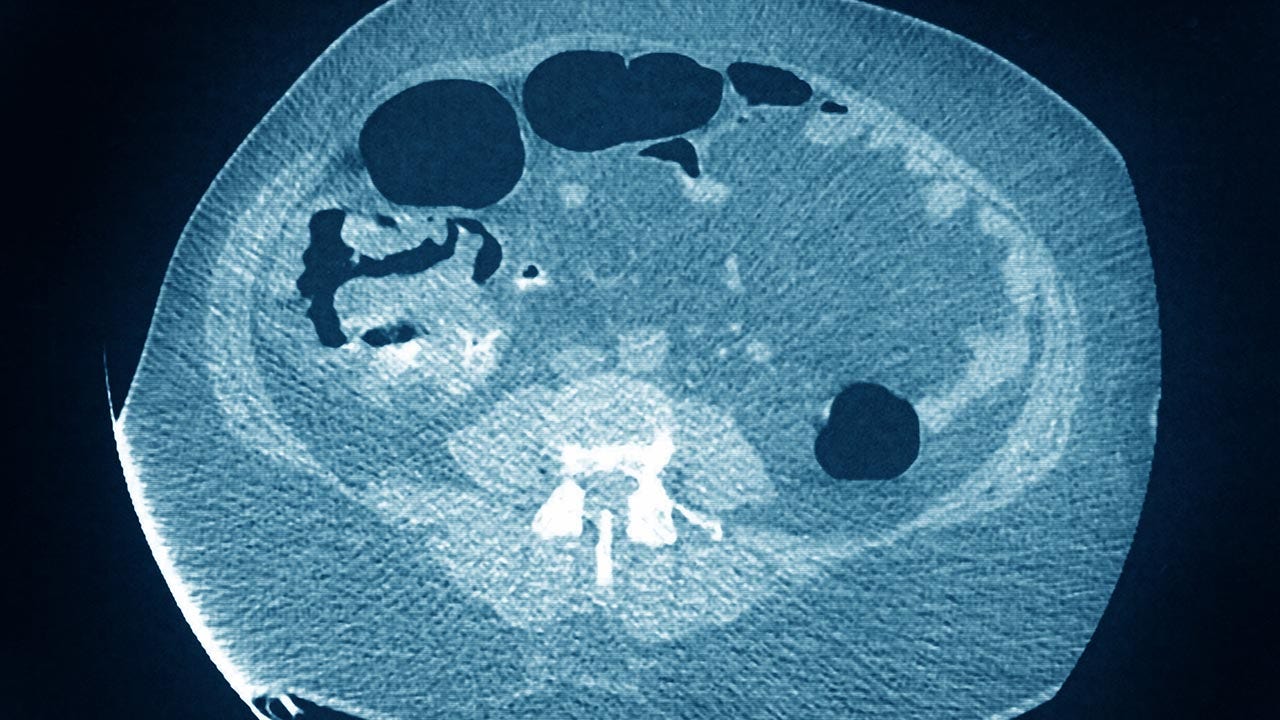

Colon cancer, along with rectal cancer, is the third leading cause of cancer deaths in the U.S., with an estimated 148,000 new cases this year.